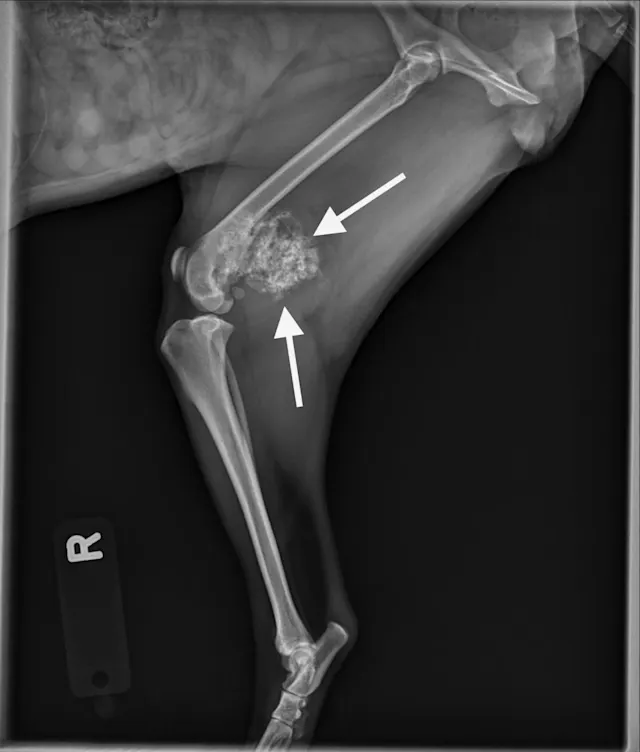

Digit melanoma

A single craniocaudal radiograph illustrates the forepaws of a 12-year-old neutered male Airedale terrier with digit melanoma. Moderate circumferential soft tissue swelling of the 5th digit of the left thoracic limb and significant lysis of the distal phalanx can be noted (arrows). The aggressive monostotic lesion of the distal phalanx of the 5th digit and associated soft tissue swelling are consistent with digital melanoma, which was confirmed via histopathology after digit amputation.